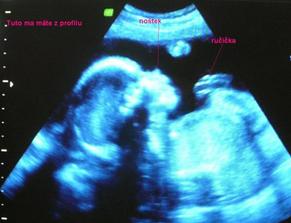

V januari sme sa dozvedeli, ze sa nasa rodinka rozrastie. 🙂 Bola to ta najkrajsia sprava. Tehotenstvo nam ubehlo ako voda a teraz uz kazdu chvilu netrpezlivo cakame prichod babatka. Uzivam si posledne chvilky s bruskom a ako kratim si cas, to tu mozete vidiet...